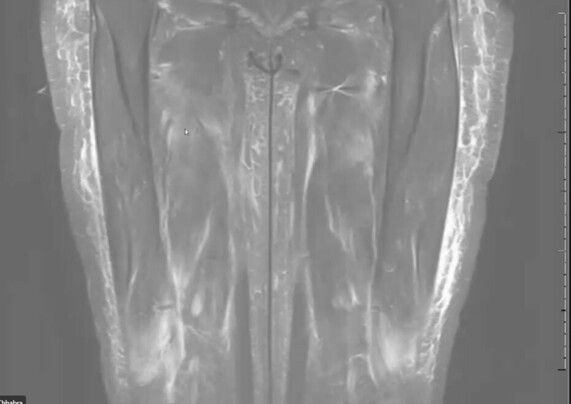

Anasarca vs myositis?

DIFFUSE edema is seen in anasarca and PATCHY edema is in myositis. In this case, the patient has both. On MRI with fat suppression, you can see the fluid as bright. โ€“ Dr. A Chhabra